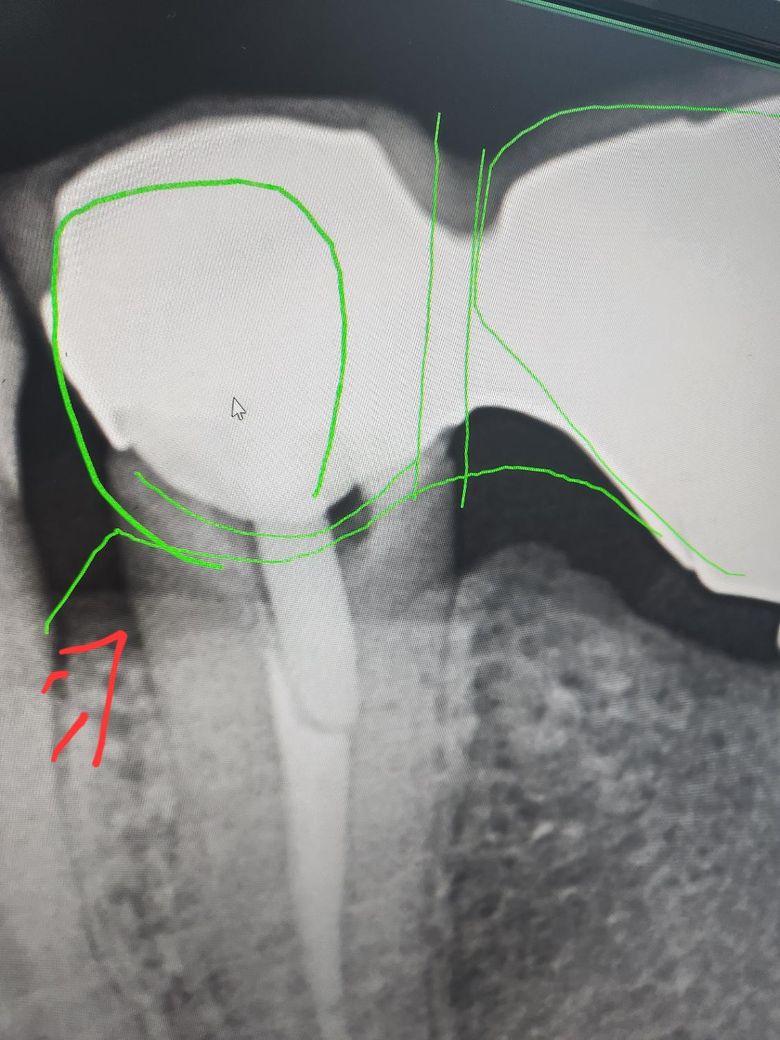

보존과 치과 선생님 계실까요~? 제가 신경치료후 크라운 해놓은 치아가 있는데, 크라운이 치아를 덜 덮어서 밑둥에 충치가 있다고 하던데, 치료가 필요한 치아일까요~? 치료 안하고 양치만 잘해서는 안되는 치아인지 여쭤봅니다. 통증은 전혀 없습니다. ㅠㅠ

• 2번 째 사진

신경치료가 되어 잇어서 통증은 없을꺼에요. 엑스레이 상으로 방사선 투과상이 보이긴 하지만, 통증이 없다면 일단은 관리하시면서 사용해보시는게 좋을것같습니다.

gap이 있어서 이차충치가 그동안 생겼을 가능성이 높은 조건이긴 합니다 신경치료 해놔서 당연히 충치 생겨도 별다른 증상은 없을 수도 있죠 엑스레이찍고 직접 치아 상태 본 치과의사가 뜯고 새로 하자고 했다면 그냥 둬서 좋을게 없는 상황인겁니다